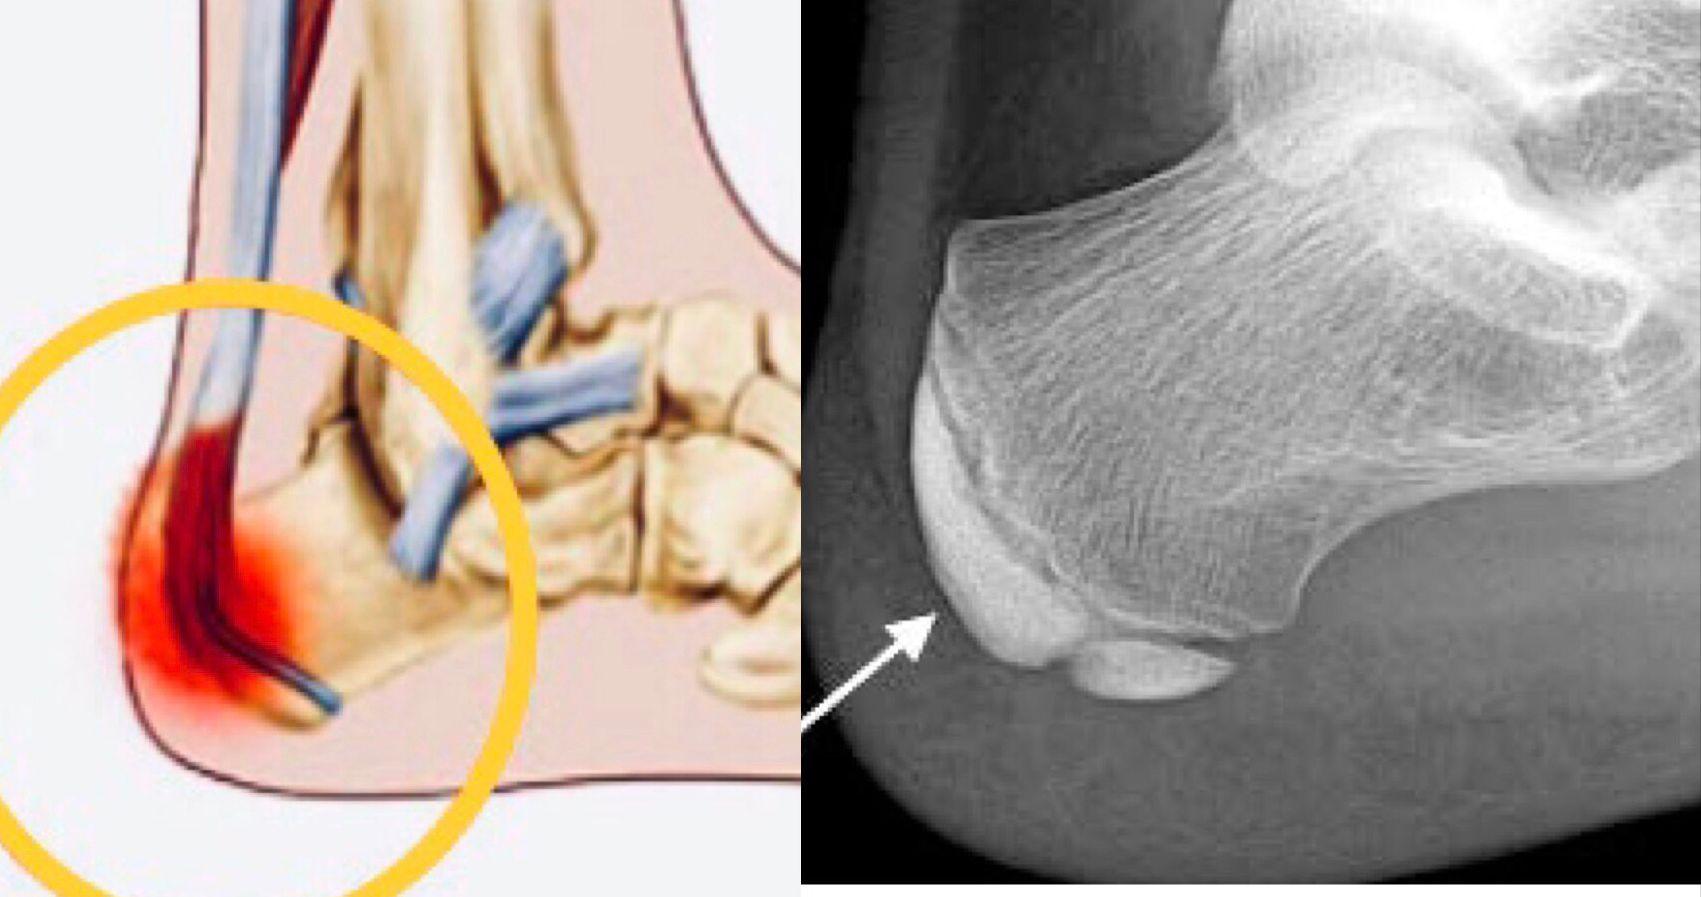

至於生長板,位於長骨兩端的軟骨區,是骨骼得以延長的關鍵部位。當青春期結束,生長板便會閉合,骨骼亦不會再變長。女孩子的生長板,通常在15至16歲閉合,而男孩子則為17至18歲。要促進骨骼健康成長,便需要營養、運動量並內分泌三方面配合。每天均衡飲食,可提供骨骼生長所需的蛋白質、鈣質和維他命D。但青少年所喜愛的高糖高鹽快餐,不但令他們減少進食高鈣食物,更會影響腸道吸收鈣質,及增加鈣質從排尿中流失。雖然沒有一項運動,與增高有高度相關性,但科學研究已證實,生長板在張力下,會加速軟骨增生,使骨骼延長。故此,多做伸展拉筋運動和吊單槓,可施加張力於骨骼。至於帶氧運動(例如跳繩和跑步),亦增加血液流經生長板,並生長激素分泌,對促進骨骼生長有正面作用。